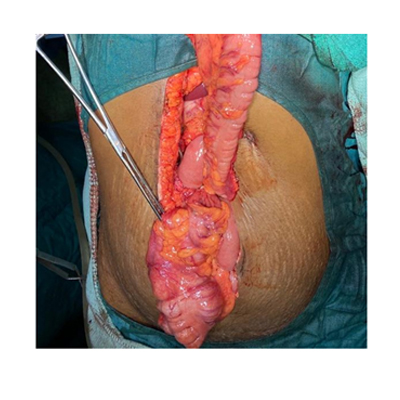

SURGERY FOR COLON CANCER

LAPAROSCOPIC SURGERY FOR RECTAL CANCER

SURGERY FOR CANCER OESOPHAGUS